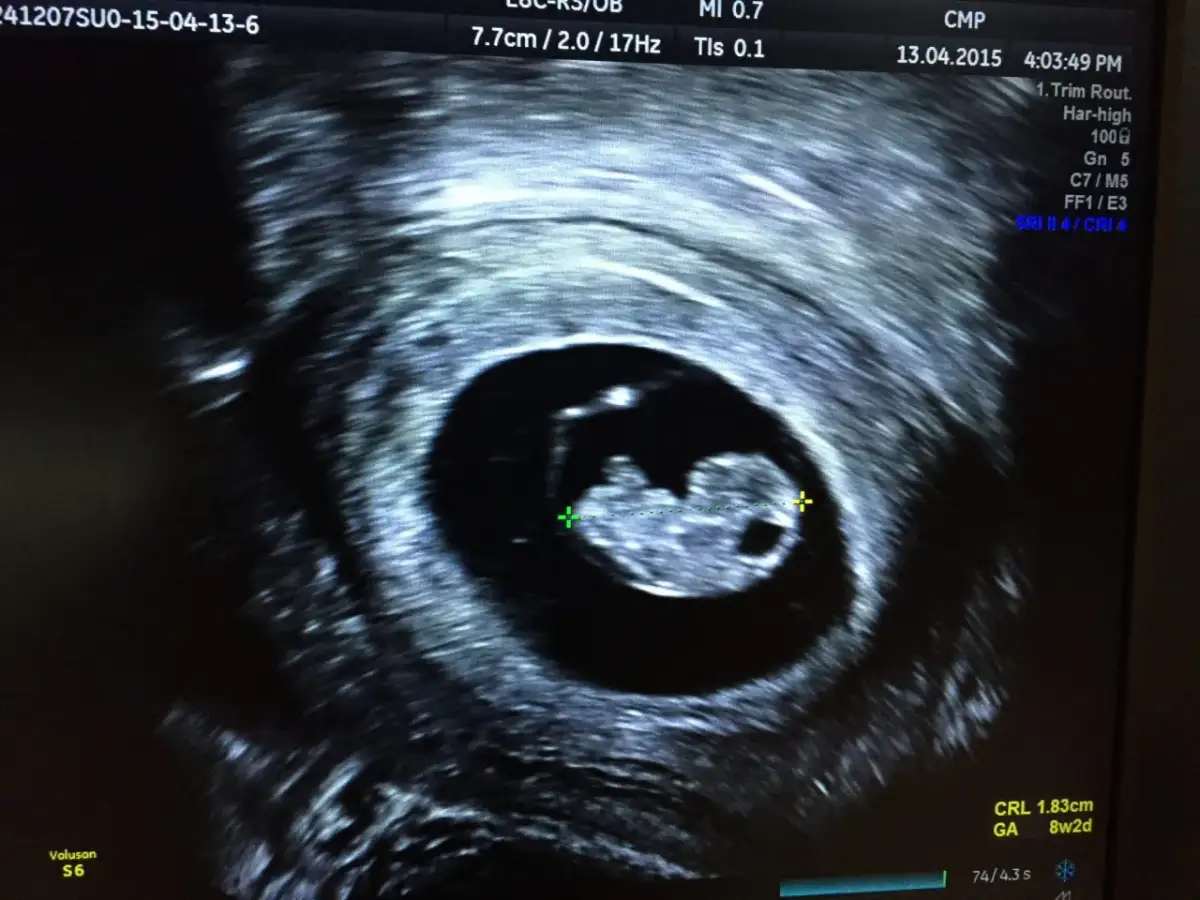

Tydzień 6-7: Moment, na który czekasz zarodek i pierwsze uderzenia serca (FHR)

To jest ten moment, na który wiele moich pacjentek czeka z największą niecierpliwością. Zarodek (zwany echem zarodka) staje się widoczny zazwyczaj około 6. tygodnia ciąży. Co więcej, między 5. tygodniem a 5. dniem a 6. tygodniem i 1. dniem ciąży, możemy już zaobserwować akcję serca płodu (FHR). To niezwykle wzruszająca chwila! Ważna zasada mówi, że czynność serca powinna być widoczna, zanim zarodek osiągnie długość 6 mm. Zarodek na tym etapie rośnie dość szybko, około 1-2 mm na dobę, dlatego każdy kolejny dzień ma znaczenie.